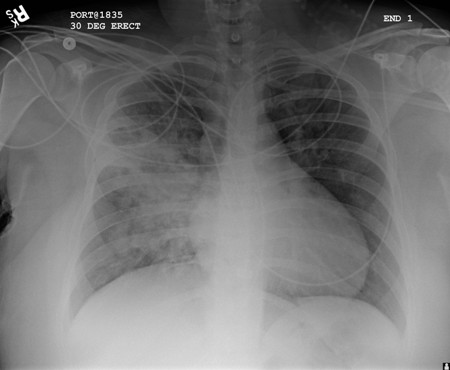

Uma radiografia torácica deve ser obtida no início da avaliação da tosse crônica.[38] Embora não seja diagnóstica das causas mais comuns, os achados podem facilmente desviar a avaliação para causas de maior gravidade como doenças pulmonares estruturais. Eles incluem câncer pulmonar, fibrose pulmonar, tuberculose, bronquiectasia, pneumonia, aspiração e sarcoidose.[Figure caption and citation for the preceding image starts]: Radiografia torácica mostrando hiperinsuflação em paciente com DPOC. A hiperinsuflação é causada pelo componente de enfisema na DPOC, em vez da bronquite crônica subjacente aos sintomas da tosseDo acervo pessoal do Dr. M. A. Sharifabadand, SUNY na Stony Brook School of Medicine, Departamento de Medicina Pulmonar e Intensiva, Mineola, Nova York, e Dr. J. P. Parsons, The Ohio State University Medical Center, Columbus; usado com permissão [Citation ends].

[Figure caption and citation for the preceding image starts]: Radiografia torácica portátil com opacidades bibasilares, com quadro mais desfavorável no lado direito que no esquerdo, em um paciente com pneumonia hospitalarDo acervo pessoal do Dr. F. W. Arnold, Divisão de Doenças Infecciosas do Departamento de Medicina, Escola de Medicina da Universidade de Louisville [Citation ends].